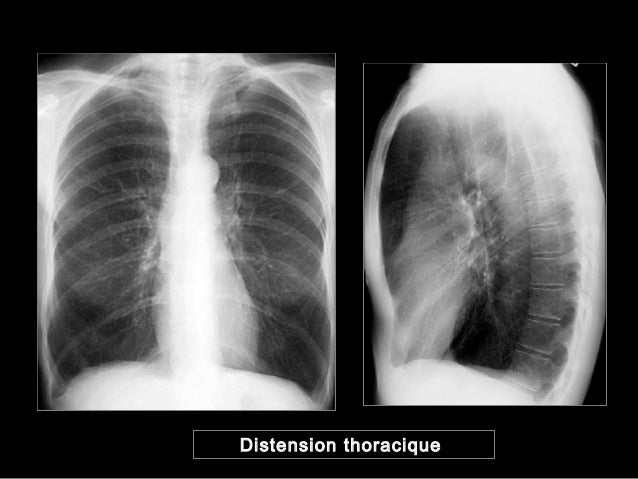

Semio radio thorax 1 Introduction à la Pathologie Thoracique 2 Les techniques d’imagerie thoracique • Complémentarité 1) par projection Radio graphie conventionnelle 2) Imagerie en coupes Échographie (plèvre, cœur) Scanner / IRM (paroi et cœur) 3) Techniques isotopiques Scintigraphie ventilation/perfusion PET/ tdm (18FDG) 4) Endoscopie bronchique (Anatomie pathologique. Abstrait Les hiles pulmonaires sont des régions anatomiques importantes à examiner sur un cliché de thorax À ce niveau transitent du médiastin vers le poumon et vice versa les troncs bronchiques principaux, les branches de l’artère pulmonaire, les veines pulmonaires, les artères bronchiques, les vaisseaux et ganglions lymphatiques, les plexus nerveux pulmonaires. Les veines bronchiques suivent les artères ;.

Semio radio thorax 1 Introduction à la Pathologie Thoracique 2 Les techniques d’imagerie thoracique • Complémentarité 1) par projection Radio graphie conventionnelle 2) Imagerie en coupes Échographie (plèvre, cœur) Scanner / IRM (paroi et cœur) 3) Techniques isotopiques Scintigraphie ventilation/perfusion PET/ tdm (18FDG) 4) Endoscopie bronchique (Anatomie pathologique. At conventional CT, they typically appear as lucent, hypovascular bands;. Cœur droit, de gros hiles pulmonaires et des opacités vasculaires pulmonaires proéminentes L’imagerie de référence de la cardiopathie est l’échocardiographie dont la portabilité, l’absence d’irradiation et la résolution temporelle sont des avantages indéniables dans cette cardiopathie L’imagerie en coupe va trouver.

IV VALEUR SEMIOLOGIQUE (5)2Syndrome de condensation pulmonaire rétractile• Compression extrinsèque / adénopathies, tumeurs thymiques, goitre• Compression intrinsèques / corps étrangers intra bronchiques, cancers bronchopulmonaires• Toutes causes d’encombrement endobronchique• Séquelles de tuberculose 75 V. Elle n’est pas bien centrée elle n’est pas réalisée en inspiration on visualise les électrodes Le cœur est gros. Les trois examens peuvent mettre en évidence des anomalies pulmonaires chez un patient atteint d'asbestose La radiographie et la scanographie permettent seulement d'observer des opacités anormales au niveau de la plèvre, mais cellesci pourraient être causées par la présence d'autres corps étrangers.